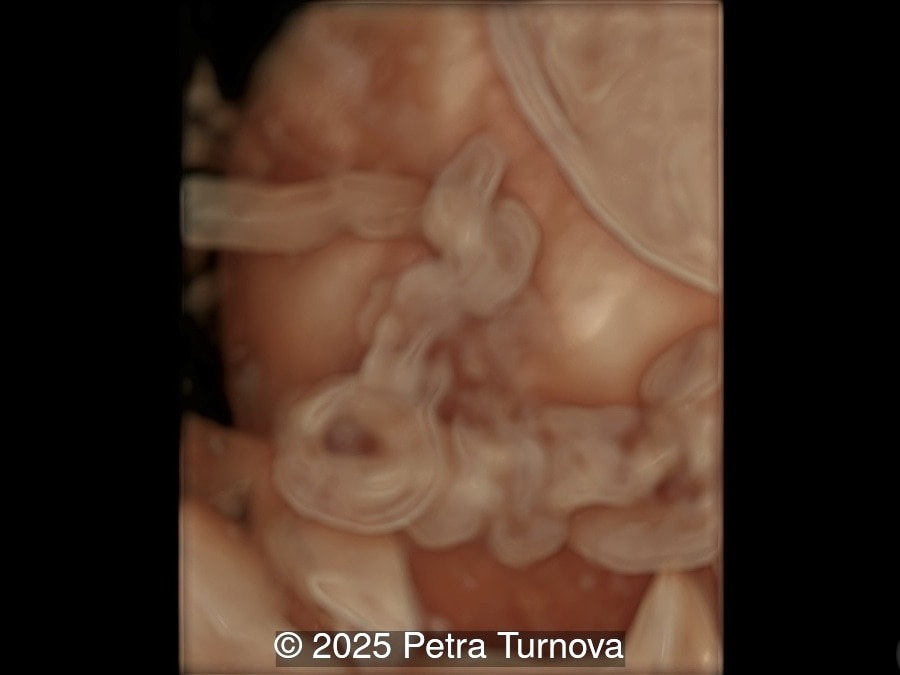

We present a case of cord entanglement. Unfortunately, the pregnancy ended in fetal demise two weeks after our exam.

Our images revealed a monochorionic monoamniotic pregnancy with entanglement of the umbilical cords. Simultaneous doppler registrations of two different heart rates suggests the cord entanglement.  There was no umbilical artery notching to suggest compromised blood flow to the fetuses.  Three-dimensional reconstructions of the umbilical cord entanglement is depicted in the images below.